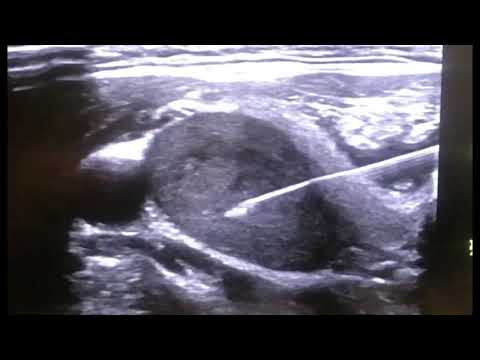

CytoCore Ultrasound Video: Thyroid

Real time and slow motion view of the CytoCore biopsing a thyroid under ultrasound guidance